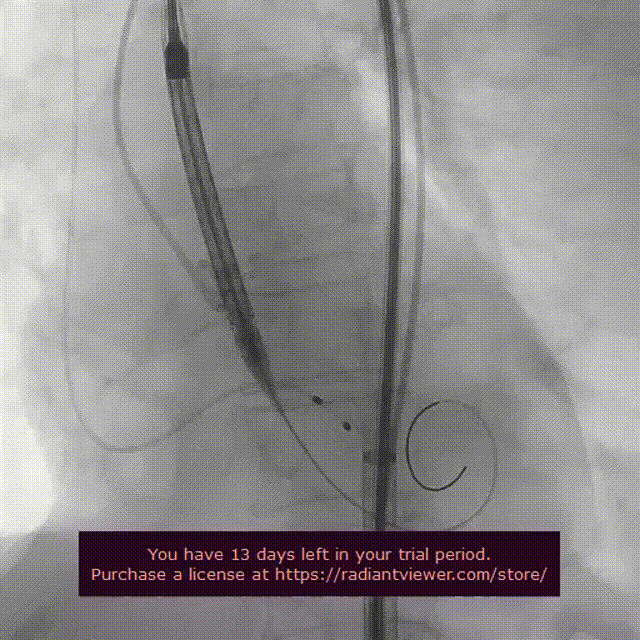

起搏150次/分,VenusA-Plus®L26标准位快速释放,释放至三分之二处,造影发现瓣膜位置不佳,下滑严重,快速进行回收,重新定位释放,造影发现第二次释放位置良好。

瓣膜位置下滑进行回收

瓣膜第二次释放造影

释放后造影观察反流消失,测压显示压差由术前的56mmhg下降至仅8mmhg。